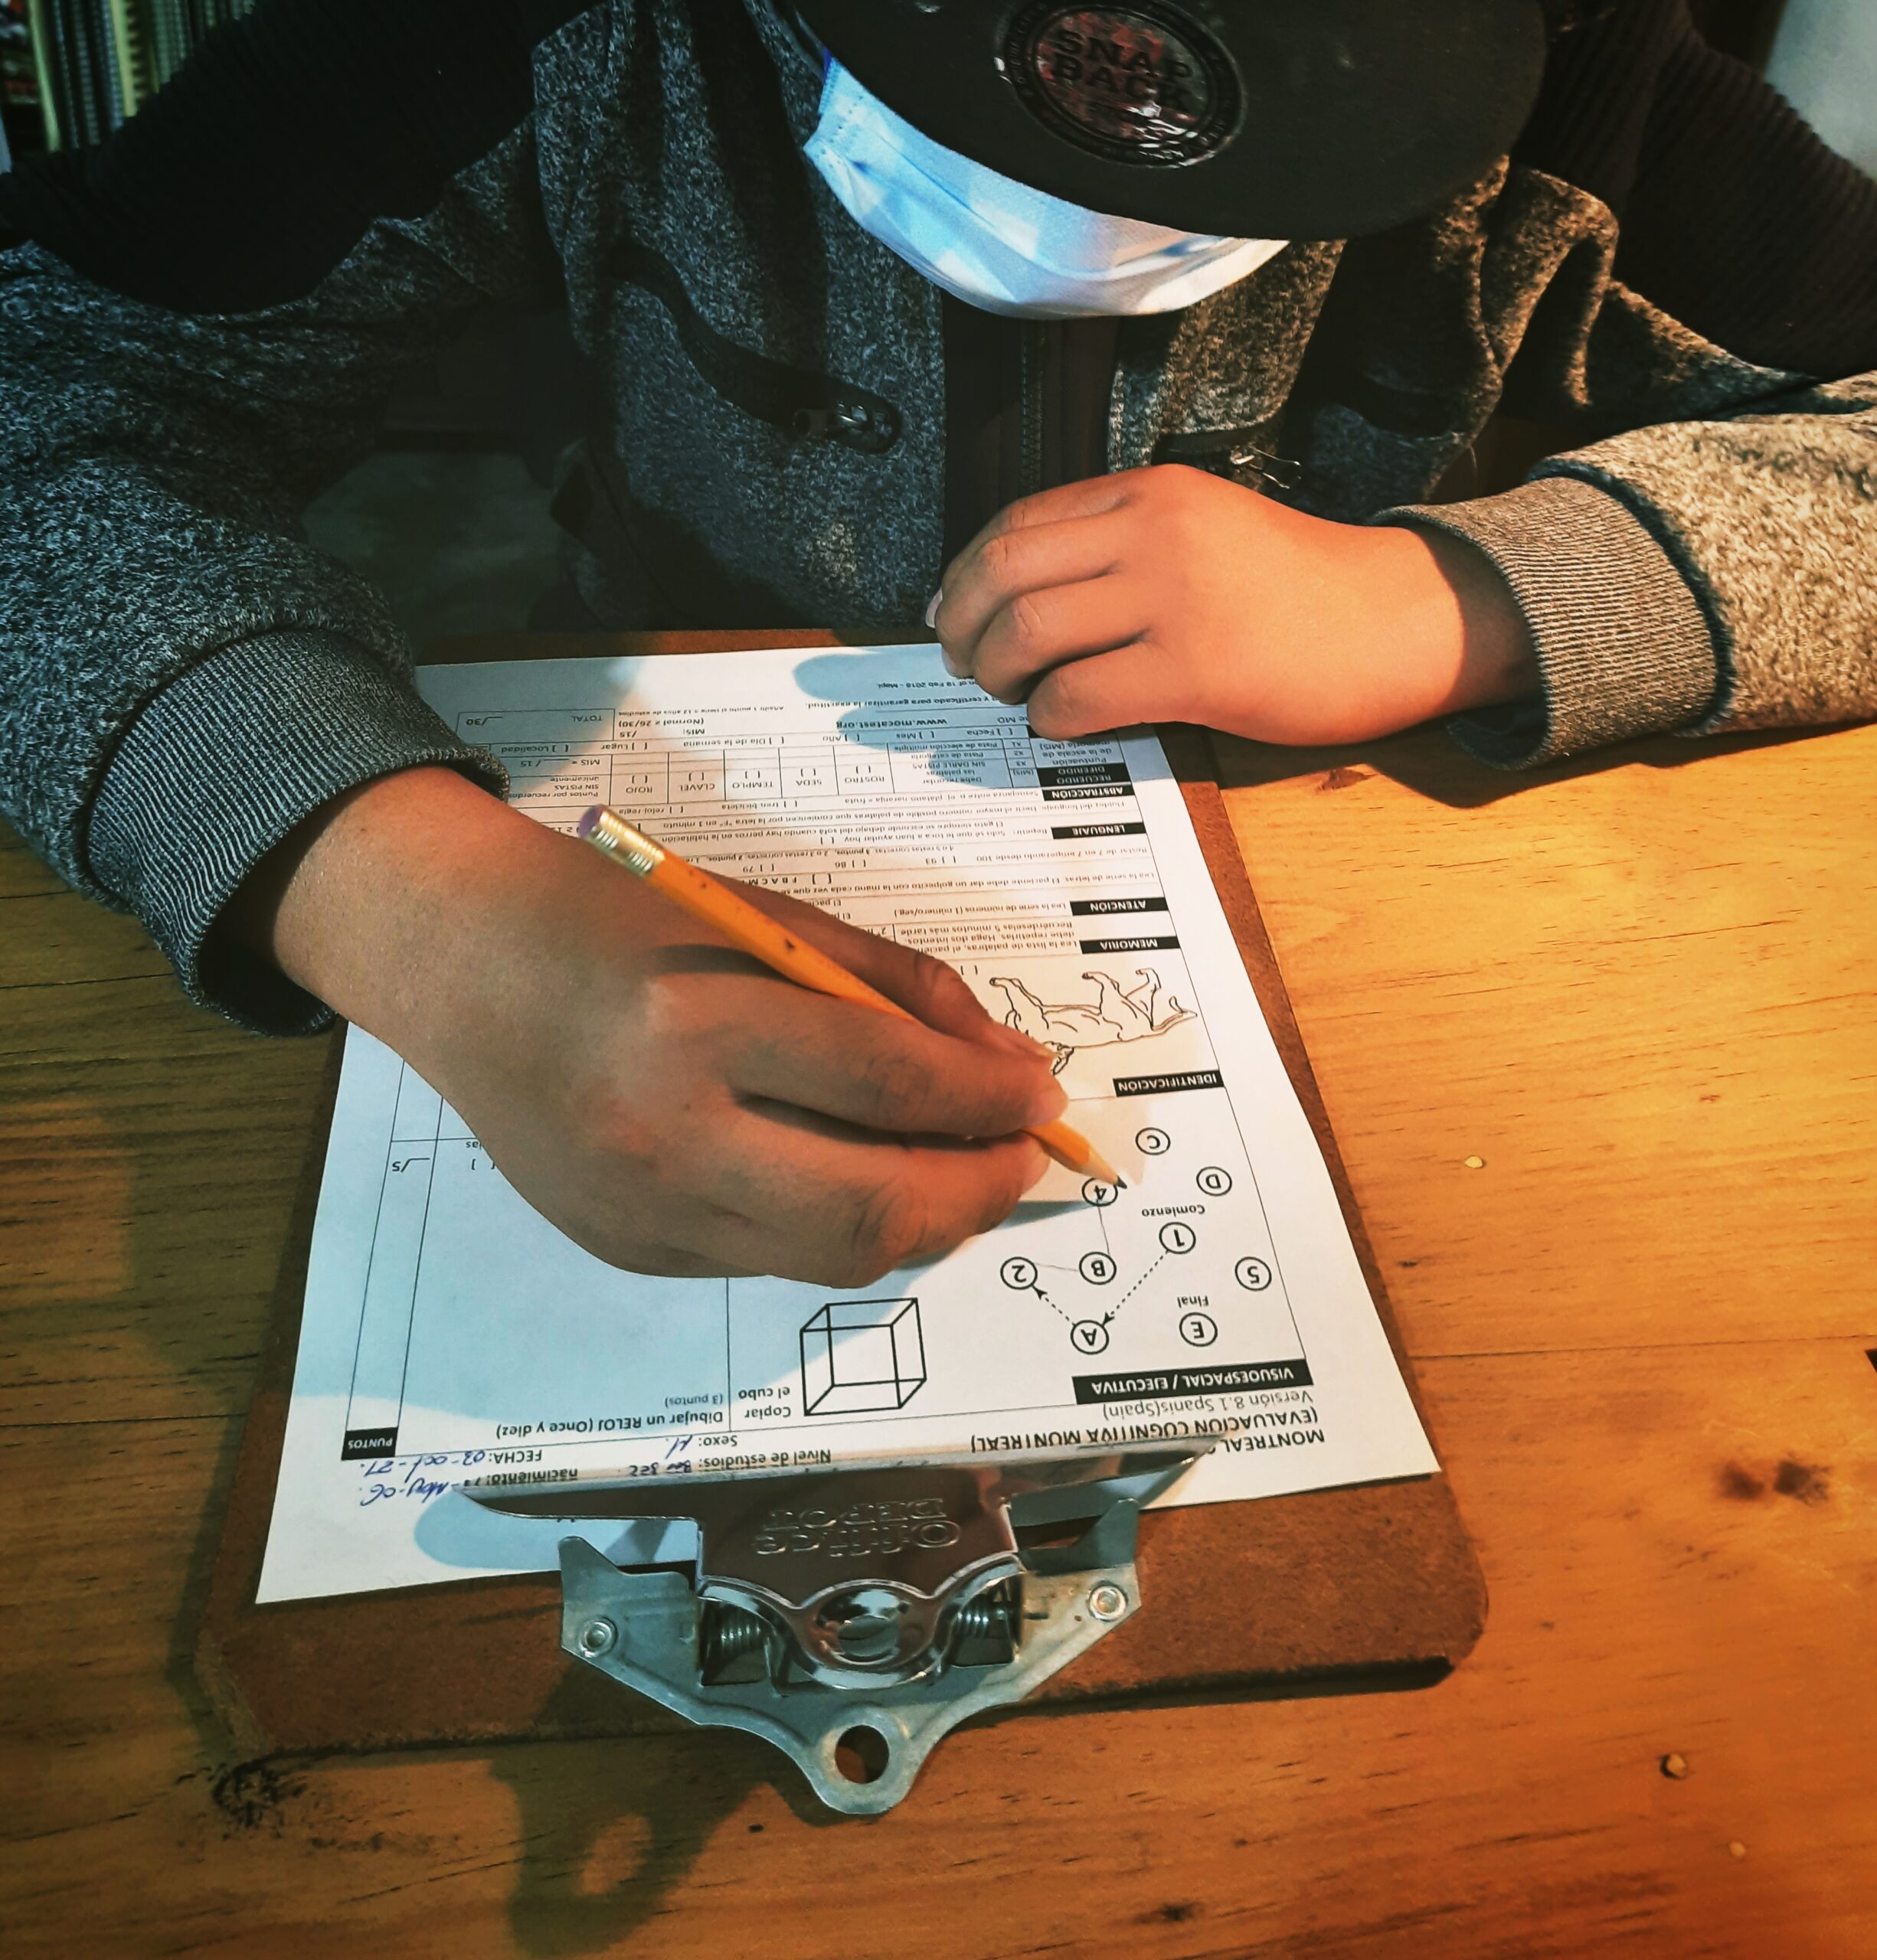

Memoria

Algunas de las zonas afectadas son las áreas entorrinales e hipotalámicas, regiones que se comunican con redes del hipocampo, como la amígdala. Esto se produce al existir una aumento de cortisol y colecistocinina, involucradas en la consolidación de la memoria, atención y ejercicios procedimentales en las áreas mencionadas.

- Martínez, D (2022). Evaluación neuropsicológica de pediátrico con Púrpura de Henoch-Schönlein [Fotografía], expediente clínico, Santiago de Querétaro, México.